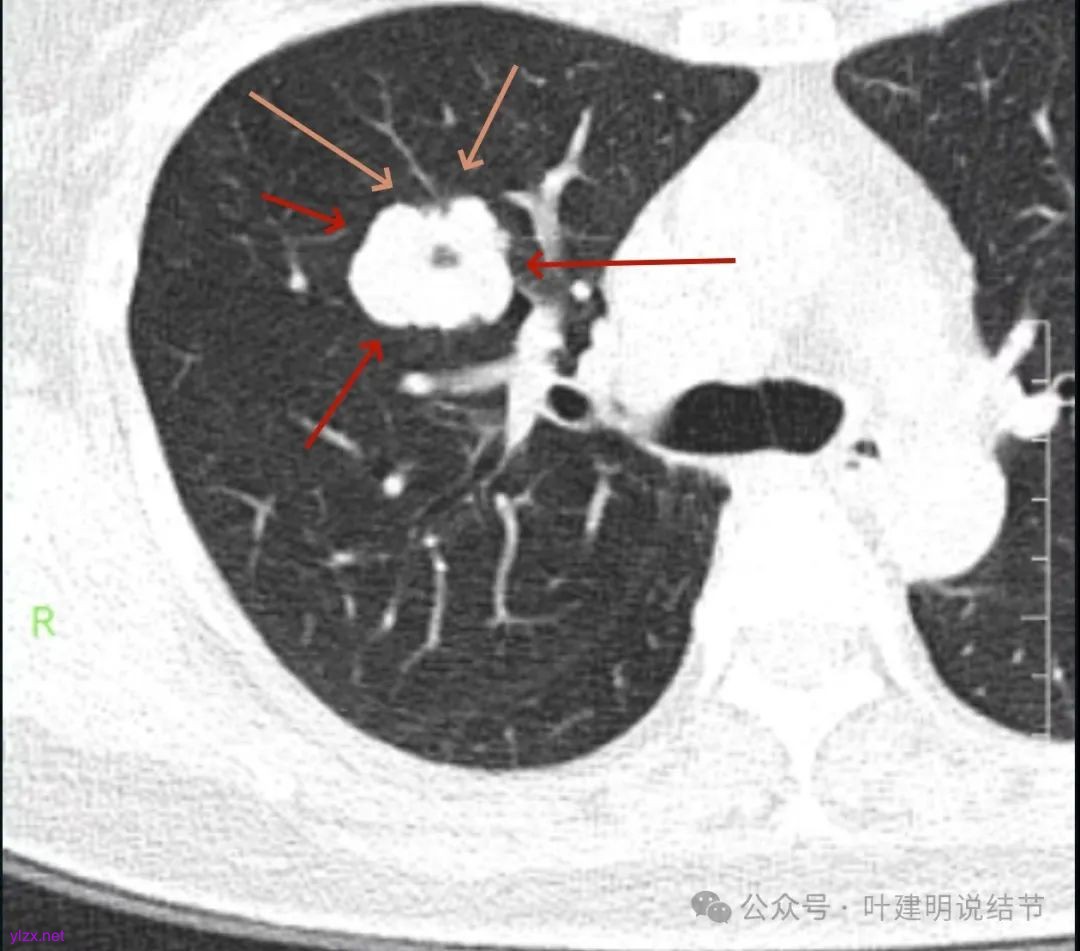

影像展示与分析:

腔静脉旁明显肿大淋巴结。

你的右上叶这个病灶基本上肯定是肺癌,要尽快处理。从影像上看有以下特点:1、整体轮廓清楚,不似普通炎症的周围有晕或阻塞性改变;2、边缘明显的浅分叶,总体上的感觉膨胀性明显,不管哪个层面看上去都是鼓鼓的;3、边缘区域有磨玻璃成分而且也是分叶状的;4、部分层面见血管进入;5、空腔病灶的壁厚薄不均,内壁不光滑。我考虑中低分化肺癌,由于腔静脉旁有明显肿大淋巴结,需要进一步完善增强CT以及PET-CT检查以明确有无远处转移,是否仍可手术治疗(从病灶本身来说是可以肺叶切除治疗的)。要尽快处理。意见供参考!